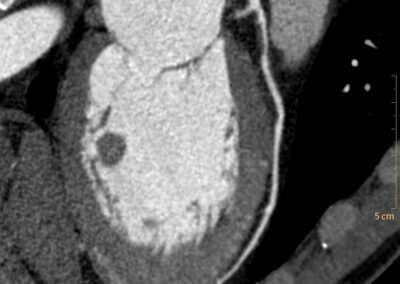

Τρισδιάστατη και δισδιάστατη απεικόνιση των στεφανιαίων αγγείων όπου διακρίνεται σημαντική στένωση λίγο μετά την έκφυσή του πρόσθιου κατιόντα κλάδου